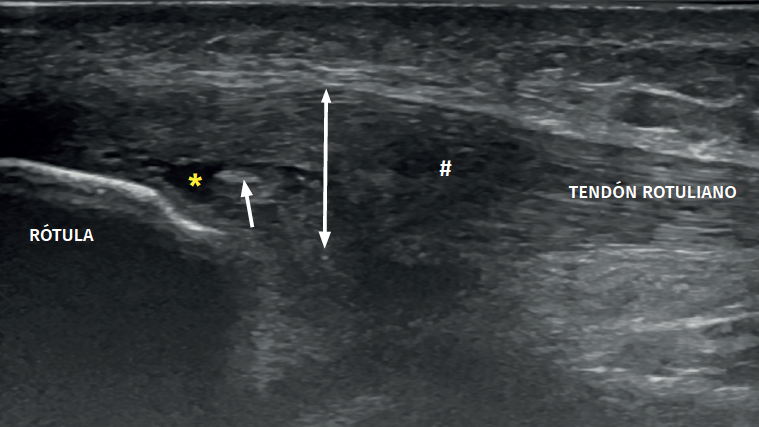

The ultrasound study of a damaged tendon evidences hypoechogenicity and loss of the fibrillar pattern, the appearance of disorganised connective tissue, and thickening of the tendon (Figure 3). In some cases we observe well delimited hypoechoic images indicating intra-substance rupture with nodular or fibrillar shapes, commonly manifesting in the deepest zone of the tendon in the lower pole adjacent to the patella (Figure 4).

Figure 4. High-resolution ultrasound study of patellar tendinopathy. Linear probe with longitudinal view. The double arrow shows increased tendon thickness, with hypoechogenic altered fibrillar pattern (#), intra-substance rupture (asterisk) and fibrosis (arrow).

In the middle portion of the tendon we may observe thickening (> 3.5 mm) associated to hypoechoic areas with zones of disorganised collagen and loss of the fibrillar pattern.

It is also common to identify cortical irregularities in the proximal enthesis of the tendon at the point where it joins the patella, involvement of the paratendon and adherences to Hoffa's fat pad. Any calcifications will be seen as white hyperechogenic zones (Figure 5).

Figure 5. Ultrasound study with high-resolution linear probe in longitudinal (A) and cross-sectional view (B). The double arrow shows increased tendon thickness associated to intra-substance lesions (asterisk) and calcifications (arrow).